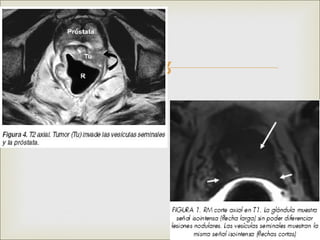

 Próstata y vesículas seminales

 CA

 Calcificaciones

 prostatitis

•   Patologías prostáticas

•   Estadificación de CA de próstata.